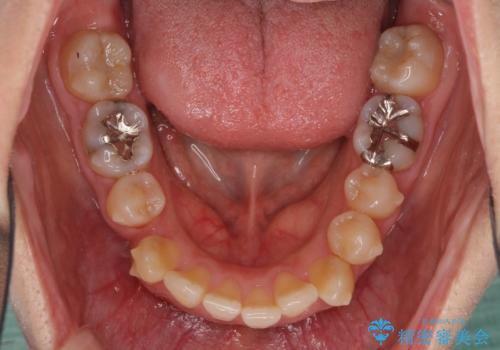

- 上下の八重歯を気にして来院された患者様です。

八重歯の後ろの歯を1歯抜歯し、補助装置(リンガルアーチ)を用いて八重歯の位置を改善し、その後インビザラインにより矯正治療を行うこととしました。

右側のみ上下小臼歯を抜歯したため、上下の正中が右にずれてしまう可能性があります。

また、元々右側は上下が咬み合っていないため、矯正をしても咬み合わないことも考えられました。

治療期間はかかりましたが、正中も合い、綺麗な仕上がりとなりました。